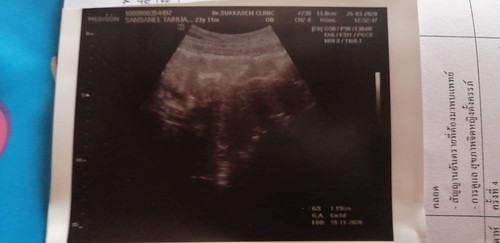

ในใบซาวด์ขึ้น 6w1d แต่ที่หมอนับจากประจำเดือนครั้งาุดท้าย 8w1d อันไหนที่น่าเชื่อกว่ากันค่ะ